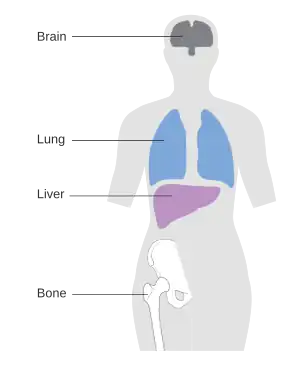

| Common sites of metastasis for breast cancer | |

Breast cancer can metastasize anywhere in body but primarily metastasizes to the bone, lungs, regional lymph nodes, liver and brain, with the most common site being the bone.[4] Treatment of metastatic breast cancer depends on location of the metastatic tumors and includes surgery, radiation, chemotherapy, biological, and hormonal therapy.[5]

Bone

Roughly 70% of all patients living with advanced breast cancer have bone metastases[9] Very often bone metastases can be successfully managed for a long time.

Brain

Brain metastasis is observed in 10% of breast cancer patients with metastatic properties[10] Many of the breast cancer therapies (like targeted antibodies) fail to penetrate the blood–brain barrier, hence allowing for tumor recurrence in the central nervous system.